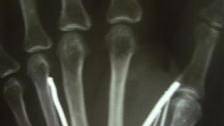

X-rays showed one- to two-inch nails in her hands and legs, with one over her eyes, officials said.

Image: Image credit: Reuters/Stringer